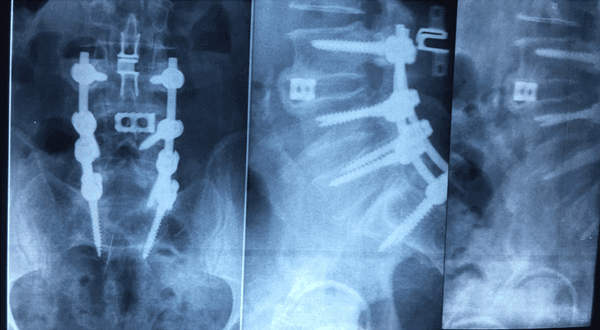

Spondilolistesi

Scoliosi

Ernia discale

Aree di competenza principali:

Chirurgia ossea

Ortopedia e traumatologia del sistema motorio

CASISTICA OPERATORIA:

Dal 1984 ad oggi il dott Antonelli ha effettuato in qualita’ di primo operatore circa 8000 interventi di Chirurgia Ortopedica con particolare prevalenza della Chirurgia dell’ Anca e del Ginocchio e della Chirurgia Vertebrale.